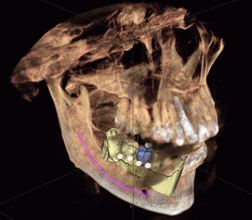

Optradam, a Dentist Tool, Utilized for Proper Jaw Manipulation During TMJ Arthroscopy and Arthroplasty

Reda Fouad Elgazzar BDS, MSc, PhD, FRCDC (C.), RCPS (Glasg.)1*, Ahmed Almuzayyen2